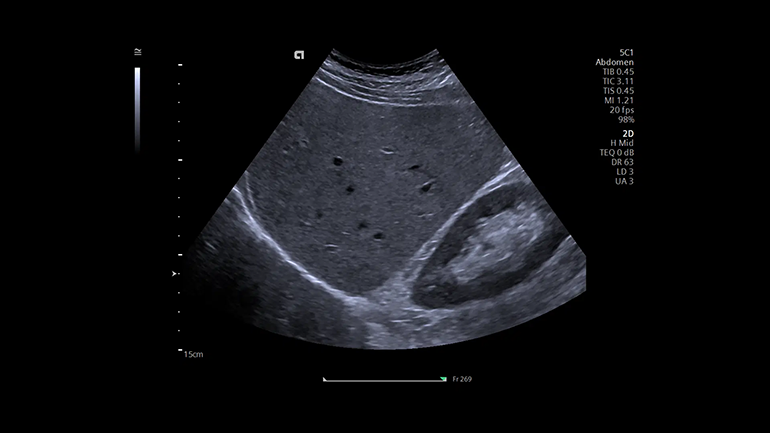

Технология когерентного формирования изображений (CIF). При работе с данной технологией для формирования изображения используется как амплитуда, так и фаза ультразвукового луча, что обеспечивает более высокое разрешение и высокую частоту кадров по сравнению с традиционными ультразвуковыми системами Высокая разрешающая способность благодаря матричному монокристальному датчику с фазированной решеткой. Основой любого датчика является пьезоэлектрический преобразователь. Монокристальная матричная конструкция датчиков обеспечивает высокую чувствительность получаемого изображения и широкую полосу пропускания при проведении наиболее важных исследований с помощью абдоминальных и кардиологических датчиков. Более широкая полоса пропускания эхо-сигнала улучшает визуализацию на глубине, разрешение по вертикальной оси и чувствительность, обеспечивая таким образом большую глубину проникновения и четкость получаемых изображений.

Высокая разрешающая способность благодаря матричному монокристальному датчику с фазированной решеткой. Основой любого датчика является пьезоэлектрический преобразователь. Монокристальная матричная конструкция датчиков обеспечивает высокую чувствительность получаемого изображения и широкую полосу пропускания при проведении наиболее важных исследований с помощью абдоминальных и кардиологических датчиков. Более широкая полоса пропускания эхо-сигнала улучшает визуализацию на глубине, разрешение по вертикальной оси и чувствительность, обеспечивая таким образом большую глубину проникновения и четкость получаемых изображений. Технология UltraArt — одновременный вывод четырех изображений в режиме реального времени на сенсорный экран с предустановленными различными настойками визуализации. Инновационная технология обработки эхо-сигнала UltraArt Universal Image Processing компании Siemens Healthineers позволяет выводить изображения на экран с предустановленными программными настойками. Выбор параметров визуализации можно определить одним нажатием кнопки на четырехкадровом дисплее в режиме реального времени. Эта технология позволяет улучшить контрастное разрешение различных анатомических структур, повысить качество и уровень согласованности исследований среди разных пользователей благодаря исключению возможности выбора неправильных сочетаний отдельных параметров сканирования.